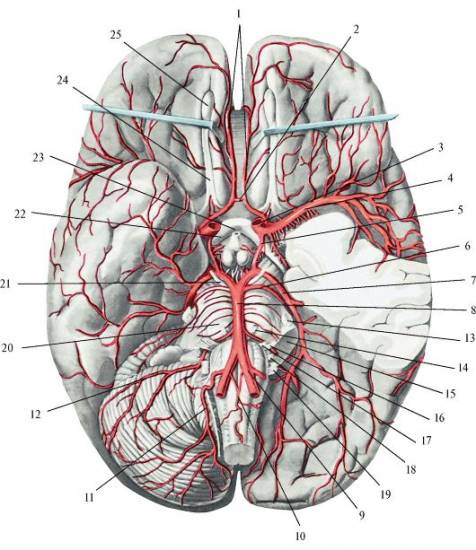

Первым делом важно понять, что же из себя представляет Виллизиев круг (ВК). По сути, это анастомоз мозговых артерий, имеющий овальную форму.

Первооткрывателем этого образования стал британский ученый по имени Томас Уиллис. Как известно, Виллизиев круг образуется несколькими артериями, среди которых:

- внутренние сонные;

- соединительная;

- задняя и передняя мозговые.

Основная функция системы заключается в обеспечении достаточного кровотока отдельных участков мозга человека. Это крайне важно при различных нарушениях кровоснабжения в шейных артериях.

Обеспечение полноценной работы круга достигается благодаря тому, что сонные артерии коммутируют не только друг с другом, а еще и с позвоночной системой. Подобная схема дает возможность на постоянной основе обеспечивать поступление питательных веществ в область головного мозга.

Строение Виллизиева круга включает в себя несколько крупных артерий, таких как передняя и задняя мозговые артерии, а также базилярную артерию. Эта сложная сеть сосудов обеспечивает не только защиту, но и оптимальное распределение крови, что особенно важно для поддержания нормальной функции мозга.